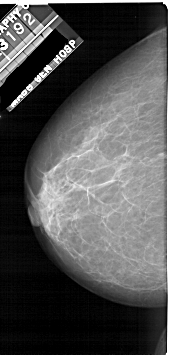

A_1922_1.LEFT_CC

LEFT_CC LINES 5311 PIXELS_PER_LINE 2536 BITS_PER_PIXEL 12 RESOLUTION 43.5 NON_OVERLAY